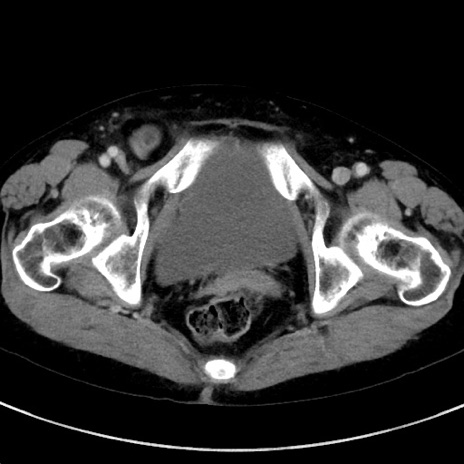

症例23(横断像)

【症例】70歳代女性

【主訴】下腹部痛・嘔吐

【現病歴】2日前より腹痛あり。昨日嘔吐あり。症状改善しないため来院。

【既往歴】胃GISTに対して胃部分切除後。

【身体所見】BT 37.1℃、BP 128/77mmHg、腹部:平坦・軟、下腹部に圧痛あり。

【データ】WBC 10200、CRP 0.31